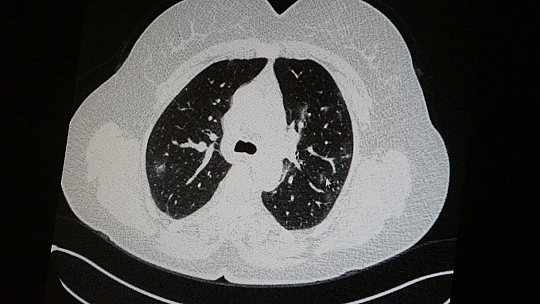

Elazığ'da öksürük, halsizlik, yorgunluk ve çabuk yorulma gibi şikayetlerle hastaneye başvuran ve korona virüs tespit edilen 2 genç hastadan aşısız olanının tomografi sonuçlarında virüsün akciğerlerde zatürreye sebebiyet verdiği görüldü. Aynı şekilde aşı olup korona virüs hastalığına yakalanan bir başka genç hastanın bilgisayarlı akciğer tomografisinde akciğerinde herhangi bir sorunun olmadığı belirlendi.

Medical Park Elazığ Hastanesi Göğüs Hastalıkları Uzmanı Dr. Cebrail Azar, geçtiğimiz yıla oranla yoğun bakımda yatan hastaların yaş ortalamasının 65’ten 35’lere kadar düştüğüne dikkat çekti. Genç olduğu halde aşı olmayanlarda hastalığın ağır seyrettiğini ifade eden Uzm. Dr. Azar, "Ben gencim, benim bağışıklık sistemim kuvvetli" diyen genç bir hastanın akciğerlerinde ciddi lekelenmelerin olduğunu ve korona virüs zatürresi olduğunu gördüklerini belitti. Uzm. Dr. Azar, aynı şekilde aşı olup korona virüs hastalığına yakalanan bir başka genç hastanın akciğer tomografisinde akciğerde herhangi bir sorunun olmadığını ve hastanın durumunun iyi olduğunu gözlemlediklerini kaydetti. Uzm. Dr. Azar, sürekli şahit oldukları "Keşke biz aşı olsaydık" sözünü bir daha duymamak için herkesi aşı olmaya davet etti.